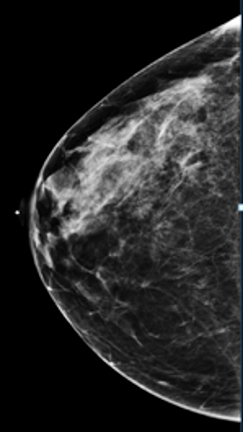

Compare these two images. You can see the benefits of 3D tomosynthesis. A small cancer (circled) on tomosynthesis slices in image A (left) is not apparent in the standard 2D mammogram, image B (right) of the same patient and same projection.

A standard 2D digital mammogram is a common method, and some facilities in the United States perform only these screenings. Digital mammograms are superior to film-screen mammograms, which are being phased out. Now, 3D breast imaging, or tomosynthesis, is a common method.

Current scientific literature suggests that this is superior to the traditional 2D mammograms, which has some disadvantages.

In 3D tomosynthesis, thin slices of the breast are obtained, and evaluation of the breasts is like flipping the pages of a book. This makes the examination more sensitive, improving the ability to detect invasive cancers by 15 to 22 percent, and reduces the likelihood of false positive and false negative results. (Breast Cancer Screening Using Tomosynthesis in Combination with Digital Mammography. JAMA 2014; 311 (24)2499-507. Sarah Friedewald et al).